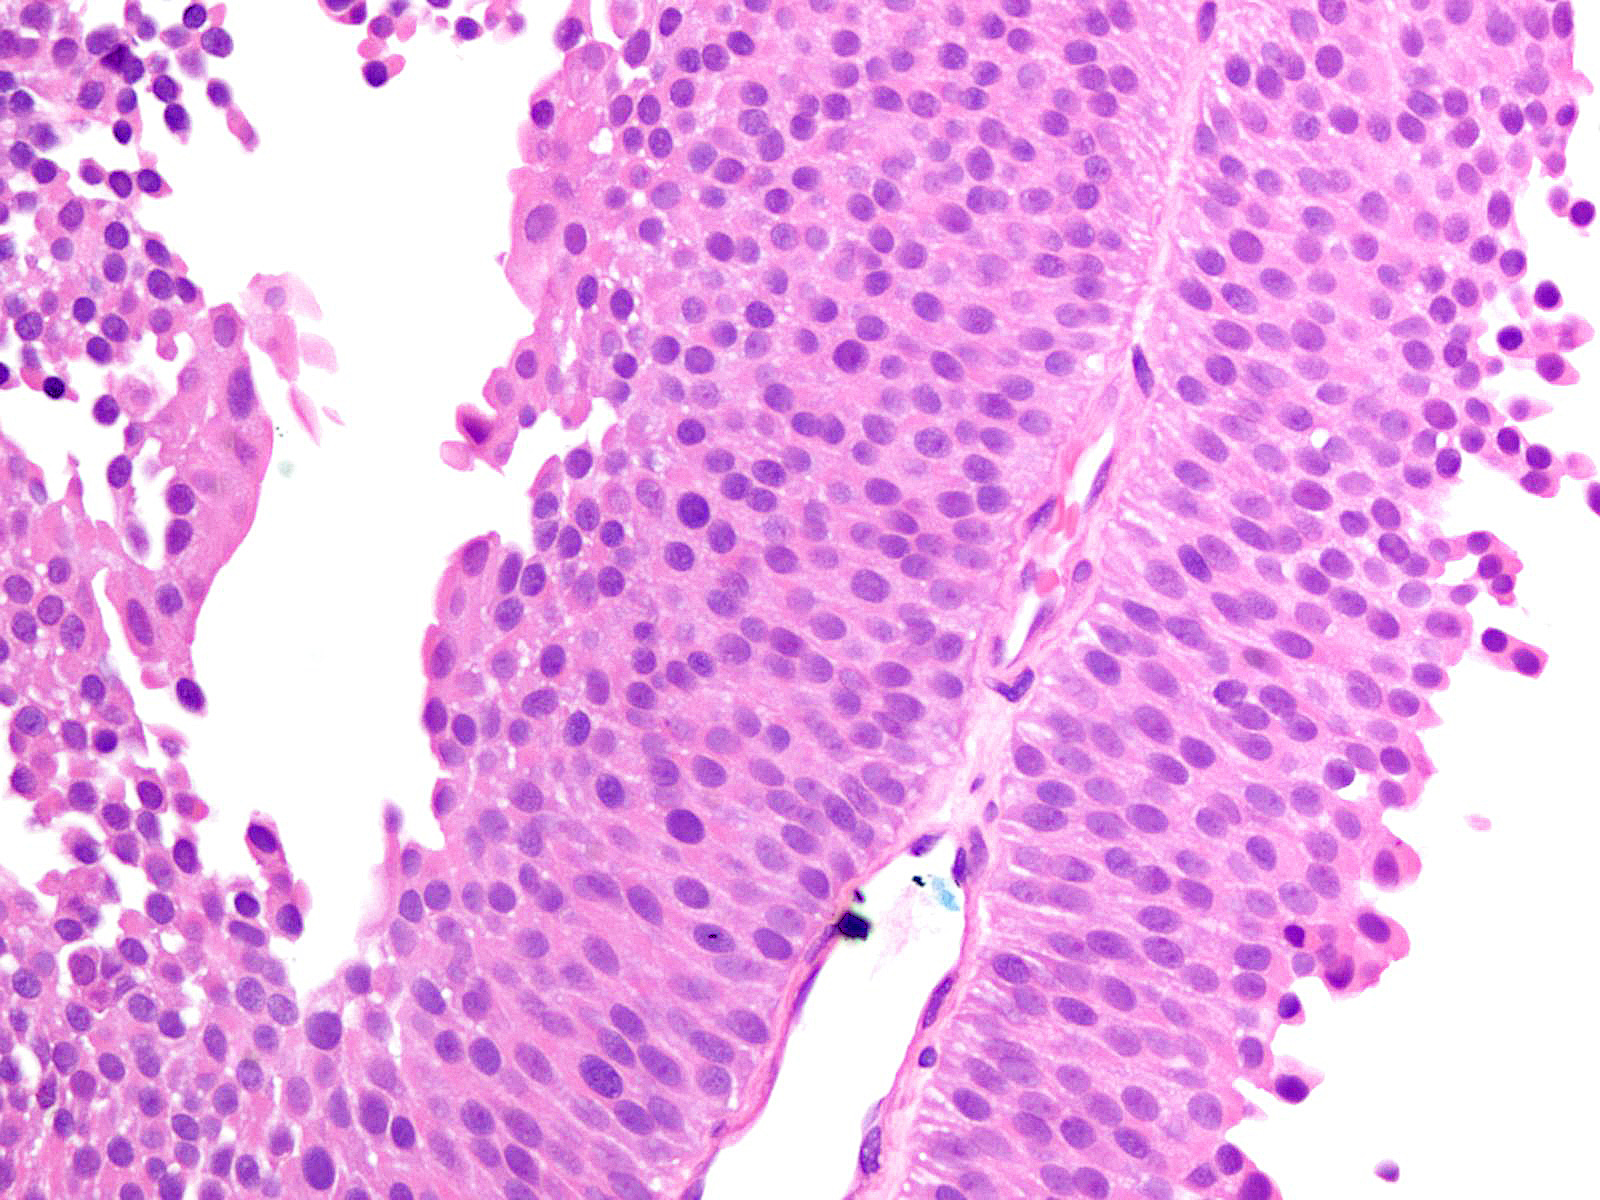

Bladder Papillary Lesions

Case ID: 149